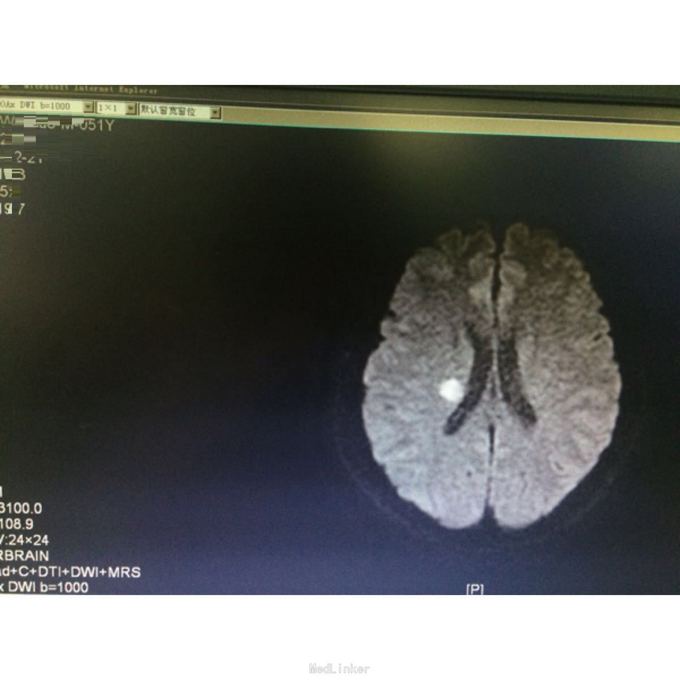

查体:言语清,对答可。左侧肢体肌力5-级,病理征未引出。 辅查:头颅MR示:右侧放射冠、基底节区、颞叶急性脑梗塞。心彩示可疑小孔房缺。锁骨下、颈部血管彩超未见明显异常。血脂正常。

诊断:脑梗死(右侧放射冠、基底节区及颞叶,急性期),高脂血症,房间隔缺损。 予双联抗血小板、克赛、强化他汀、改善循环治疗,辅以针灸、康复锻炼治疗。